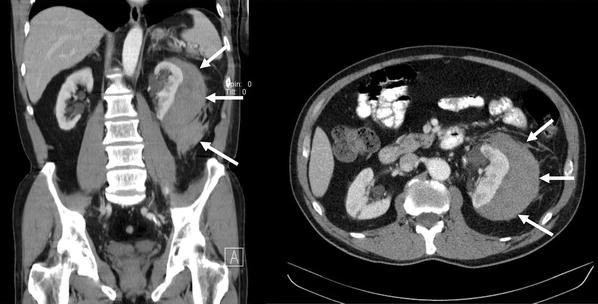

一名在 SWL 期间出现急性疼痛的患者(患者 #6)出现急性血红蛋白从正常水平下降至 9.0 g/dl 。 由于血压为 160/90 mmHg , 他在干预前接受了 10 mg 硝苯地平舌下注射 。 CT 扫描证实了 17 × 15 cm 的 RHT 包膜外延伸 , 没有活动性出血的直接迹象(图 2 ) 。 通过最初的保守方法 , 患者稳定下来 。 由于尽管使用了大剂量镇痛剂 , 但仍存在持续强烈且无法控制的疼痛 , 并且尽管使用了抗生素预防措施 , 但感染水平仍在增加 , 因此该患者在入院 5 天后接受了开放性腰椎血肿清除术 。 术中检查未发现活动性出血 。 RHT 几乎完全排空 , 部分完全脱膜的肾脏在止血垫的帮助下成功幸免 。 进一步的住院治疗很顺利 。

6 号患者接受手术前 RHT 的 CT 扫描 。 用箭头标记的 RHT